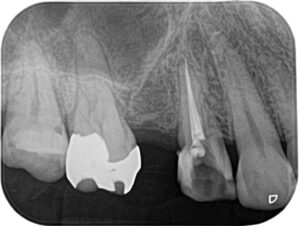

(画像: xray_rc1.jpg 治療中のX線画像。根管の形態を確認しながら慎重に処置を行いました。)

MTA根充と補綴準備

根管内を乾燥させた後、MTAセメントを用いて根管を密封(根充)しました。

MTAは高い封鎖性と生体親和性を持ち、炎症の再発防止に優れています。

根充後は仮封を行い、2回目の来院時に最終的な補綴物(被せ物)の準備を行いました。